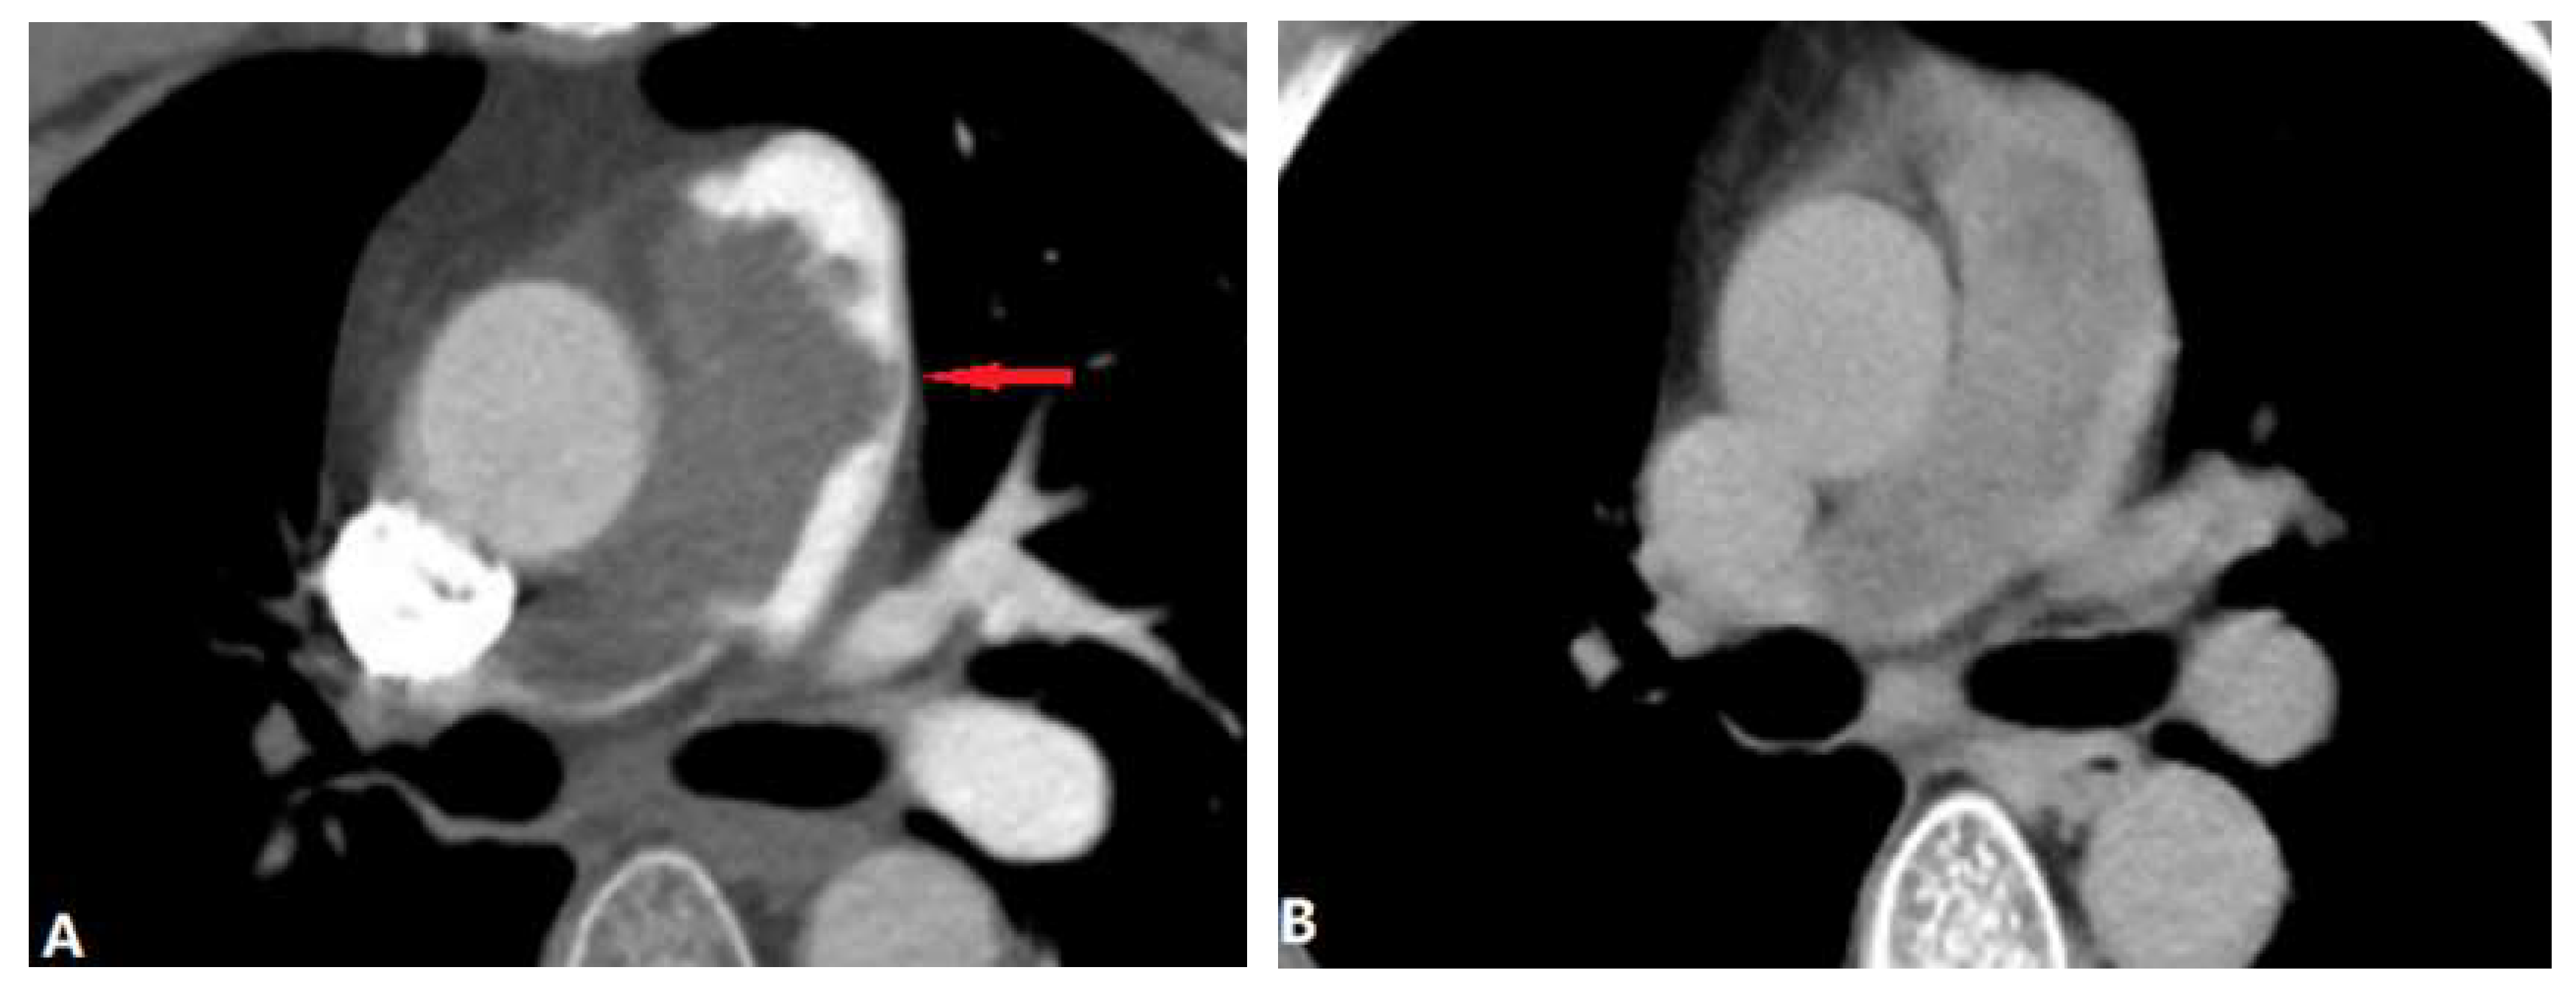

3.2.2. Arterial Dissection (AD)

3.3. Extraluminal Abnormalities